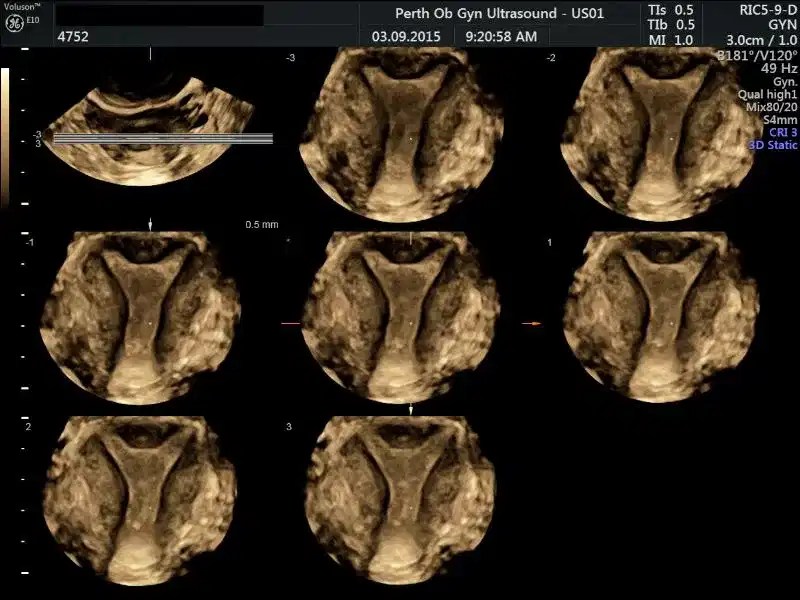

from pogu.com.au

Pelvic Ultrasound POGU